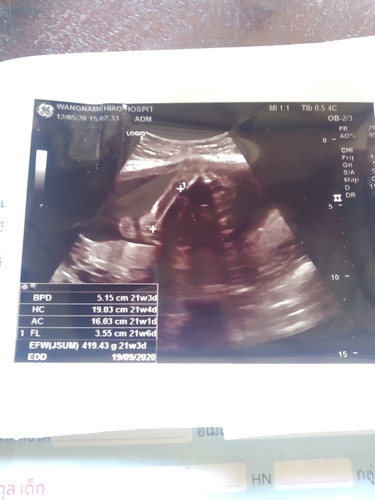

ผู้หญิง หรือ ผู้ชาย

ใครดูออกว่าผู้หญิง หรือผู้ชายคะ

ญมั้ยค่ะ หมอว่าไงบ้างค่ะ

หม่่ามี๊ of 1 จอมซน ลูกชาย